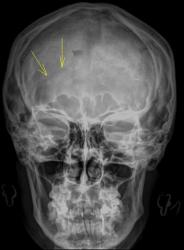

Лично я, по рентгенограммам, обратил-бы внимание на эту область.

Лично я, по рентгенограммам, обратил-бы внимание на эту область

Провокация № 1. Чем объяснить "нечеткость" задних клиновидных отростков?

Провокация № 2. Чем объясним эту линию просветления?

У женщины хорошо выражен сосудистый рисунок, по МСКТ больше к счастью нет травматических изменений.